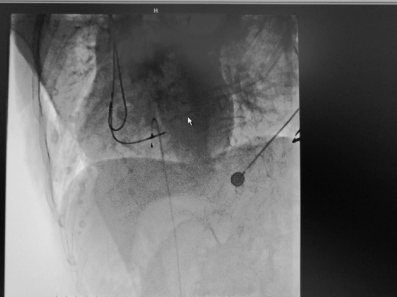

90歲高齡,3小時內(nèi)發(fā)生了3次暈厥,反復(fù)因心動過緩誘發(fā)尖端扭轉(zhuǎn)性室速并引發(fā)室顫(即心臟瀕臨停止跳動,可在一分鐘內(nèi)引發(fā)死亡),眼看生命危在旦夕,一場與時間賽跑的生命搶救行動在我院內(nèi)展開……?朱彬為患者治療中?????九旬老人頻發(fā)暈厥??醫(yī)生快速精準(zhǔn)診斷病情不久前的一天中午,正在家中休息的李婆婆突然暈倒...